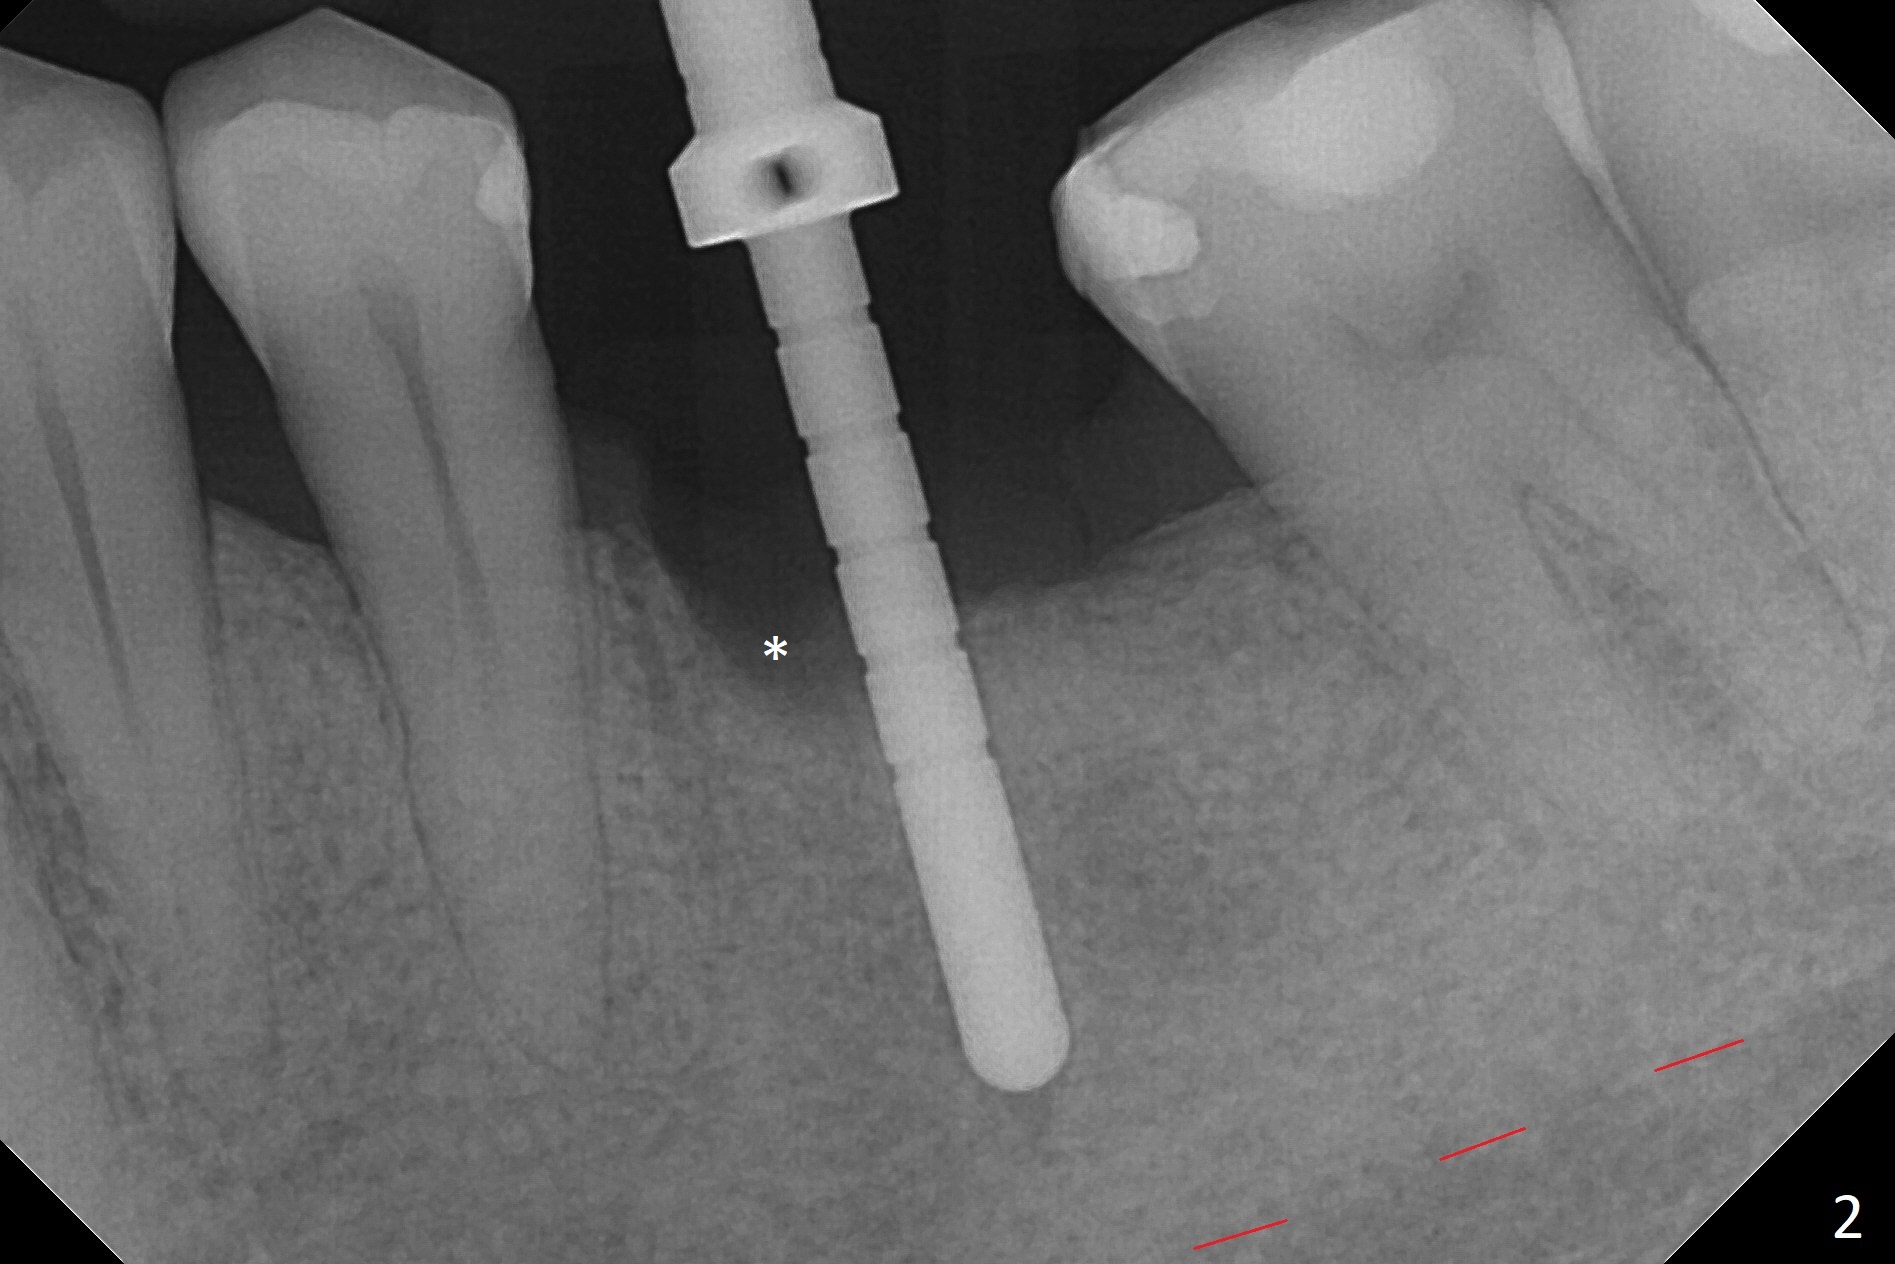

While the mesial ridge is relatively wide associated with residual root at #19 (Fig.1 <), the distal one is narrow (*). Osteotomy is initiated distal to the mesial socket (Fig.2,3 *). Due to the narrow ridge, a 4.5x11 mm implant is placed (Fig.4); before as well as after placement of a 6x4(3) mm abutment, the mesial socket (*) is filled with Vera graft and autogenous bone as well as collagen plug. Following suturing, periodontal dressing is applied to the wound. There is no apparent bone loss 7 months postop (Fig.5,6) or 14 months post cementation (Fig.7). In fact the abutment has been incompletely seated (Fig.5-8), which may be related to #13 failure. The ridge appears to be narrow for the 4.5 mm implant 1.5 years post cementation (Fig.9). When a lady looks skinny with sign of the narrow ridge, choose an implant as narrow as possible.